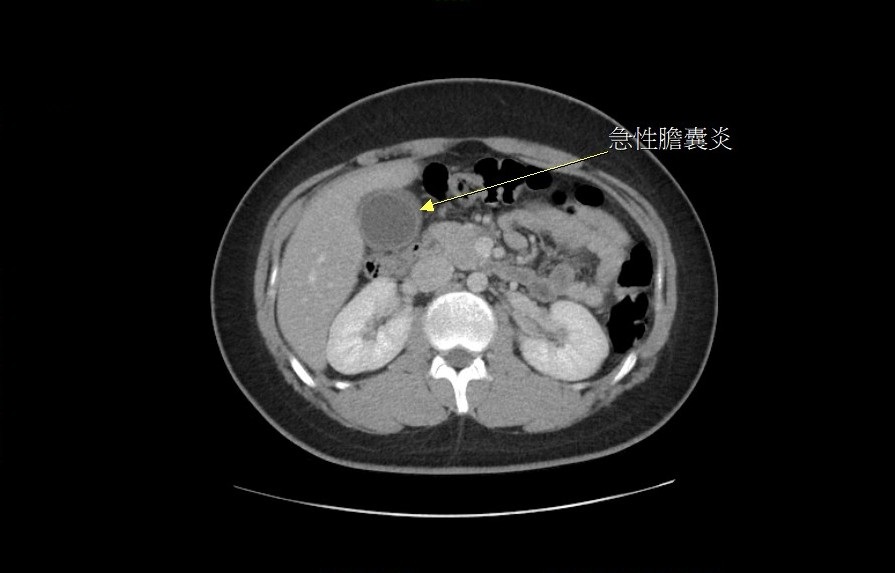

膽結石不只發生在中老年人身上!一位15歲男性國中生因上腹痛多日到急診就醫,經醫師安排電腦斷層及腹部超音波掃描後,發現兩顆分別為2.5公分及1.5公分的膽結石卡住膽囊出口,診斷為急性膽囊炎,並安排腹腔鏡手術治療。術中發現病人膽囊已嚴重發炎、壞死,幾乎已到快破裂的狀態,幸好及時摘除膽囊與結石,才不致引發腹膜炎。

檢查發現,兩顆膽結石卡住膽囊出口,診斷為急性膽囊炎。